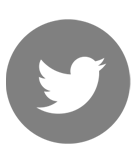

Βλέπουμε στην φωτογραφία που ακολουθεί αριστερά, τα εμφυτεύματα στην θέση των πίσω δοντιών ενώ δεξιά βλέπουμε εμφυτεύματα που τοποθετήθηκαν μετά την εξαγωγή των δοντιών κάτω από ακινητοποιημένα με σύρμα δόντια.